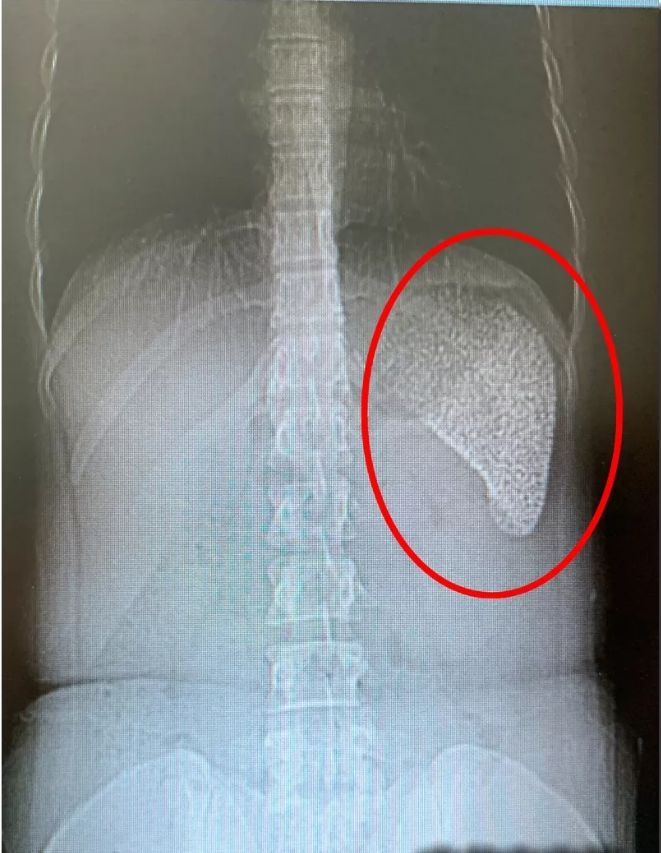

上面这就是何莉莉的CT片,图中发白的就是她的脾脏。我们知道CT成像,空心的是黑色的,完全实心的白色的。何莉莉的脾脏完全白色,也就意味着她的脾脏已经是一个实心大疙瘩,里面都是钙化点,几乎就是一块板砖了。